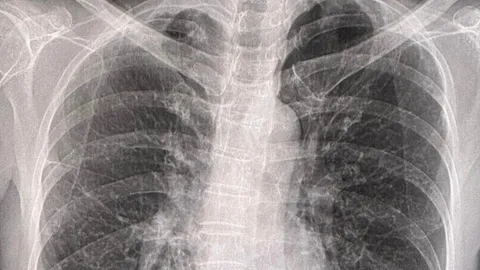

อุทาหรณ์ หญิงวัย 84 ปอดอักเสบ หลังทำความสะอาดมูลนกพิราบที่ระเบียงเป็นประจำ